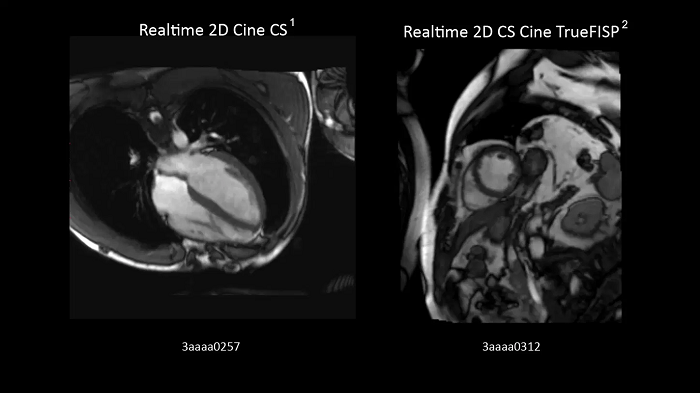

Compressed Sensing Cardiac Cine

Compressed Sensing Cardiac Cine for free-breathing Cardiac Cine imaging.

Left:

- BioMatrix Spine 32

- Body 18

Right:

Realtime 2D Cine CS. Image Credit: Siemens Healthineers

Realtime 2D Cine CS TrueFISP. Image Credit: Blemsersi Radfospital Australian, Germany